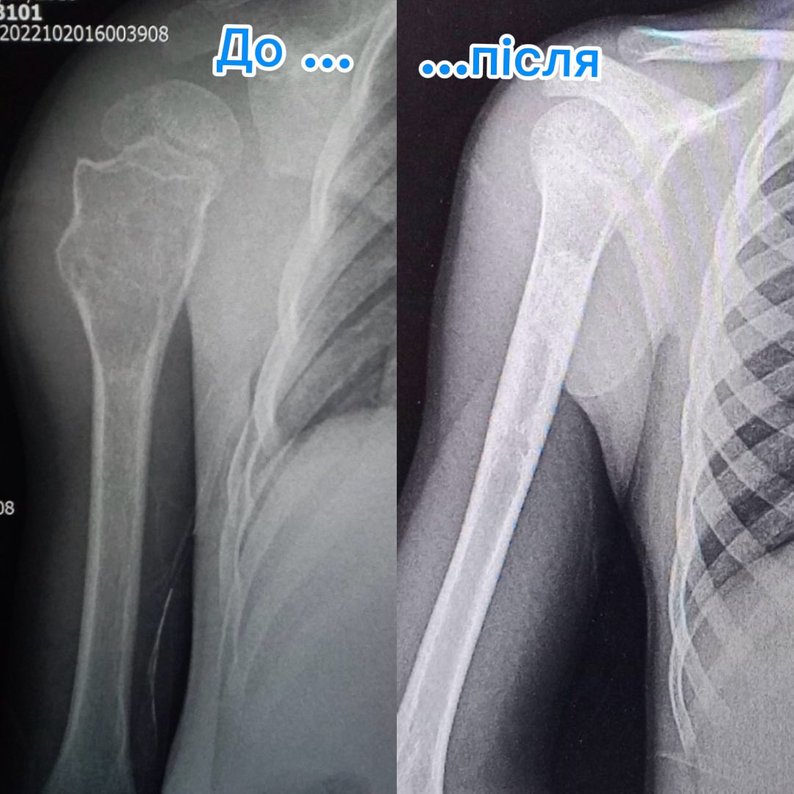

До Рівненської обласної дитячої лікарні звернулися батьки дев’ятирічного хлопчика, який скаржився на біль у плечі. Після обстеження у нього виявили кісту значних розмірів.

- Після проведення рентгенографії виявили значних розмірів кісту в проксимальному відділі плечової кістки — діагноз кісткова кіста. У цьому клінічному випадку спеціалісти ортопедо-травматологічного центру застосували метод пункційного лікування, — розповіли у лікарні.

Медики пояснили, що пацієнту тричі, з інтервалом у три місяці, виконували промивання кісти під загальним знечуленням та вводили у її порожнину спеціальний гормональний препарат.

- Метод дозволив уникнути великого оперативного втручання та забезпечив чудовий результат: рухи в плечовому суглобі повністю відновлені, дитина повернулася до активного життя, — кажуть лікарі.